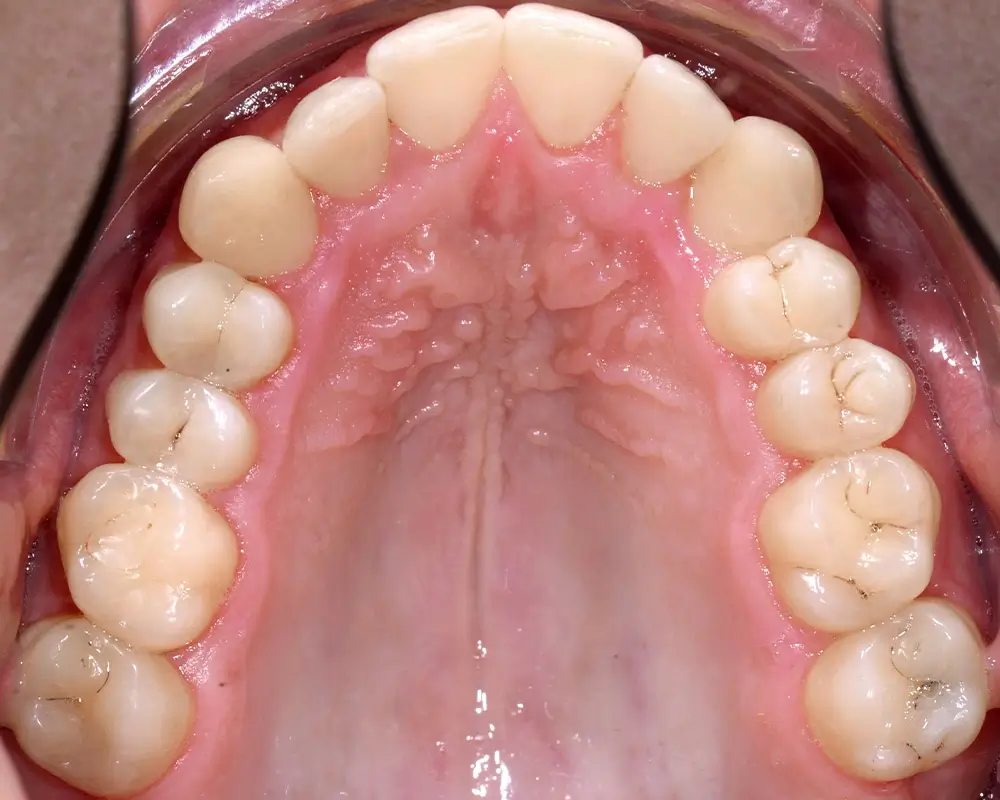

Перекрестный прикус - Кейс 5

Эффективность устранения дефекта прикуса посредством элайнеров FlexiLigner.

27

Количество кап НЧ

25

Количество кап ВЧ

Результаты лечения